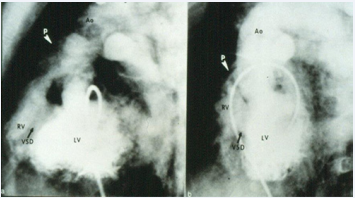

Figure 14 Selected cine frames from left ventricular (LV) angiogram in straight lateral (a) and left anterior oblique (b) views in a patient with Type I tricuspid atresia demonstrating origin of the aorta (Ao) from the LV and the pulmonary artery (P) (white arrow head) from the right ventricle (RV). A large ventricular septal defect (VSD) (black arrow) is also shown [27].

Figure 14: Selected cine frames from left ventricular (LV) angiogram in straight lateral (a) and left anterior oblique (b) views in a patient with Type I tricuspid atresia demonstrating origin of the aorta (Ao) from the LV and the pulmonary artery (P) (white arrow head) from the right ventricle (RV). A large ventricular septal defect (VSD) (black arrow) is also shown [27].

As alluded to in the preceding section, the diagnosis of TA can be made by clinical, chest X-ray, and ECG findings and confirmed by echocardiographic studies, and therefore, cardiac catheterization and selective cineangiography are not necessary to establish the diagnosis [31,37]. There is no need for cardiac catheterization even in those neonates with severe arterial desaturation; the diagnosis of TA made on the basis of clinical and echo-Doppler studies is adequate to make management decisions. However, catheterization may be indicated: 1. If balloon atrial septostomy is necessary and 2. Prior to bidirectional Glenn and Fontan surgery in order to define the pulmonary artery pressures and anatomy. For a detailed discussion of cardiac catheterization and selective cineangiography, the interested reader is referred elsewhere [31,35,37,38]; however, some typical angiographic pictures will be presented in Figures 12 to 17.